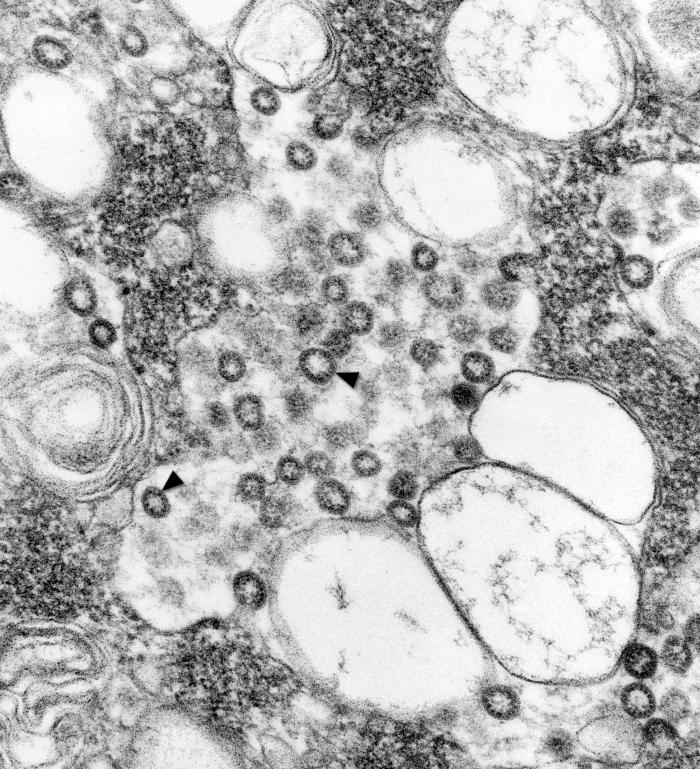

The mystery is that Helicobacter pylori, a gram-negative bacterium species typically found in the stomach, has been linked to ulcers, gastritis and gastric cancer – specifically stomach cancer. Yet most of the population of third world countries host H. pylori, with extremely low gastric cancer rates.

The strains that were growing back fast had genes recognized as CagA-positive. CagA is a part of the DNA – an oncoprotein secreted by certain species of H. pylori.

As it turns out, the CagA-negative strains of H. pylori were much easier to kill. But these are also the healthy strains of H. pylori. CagA-positive strains of H. pylori tend to carry a genotype called vacA s1. This s1m1 genotype is linked to gastritis and cancer.